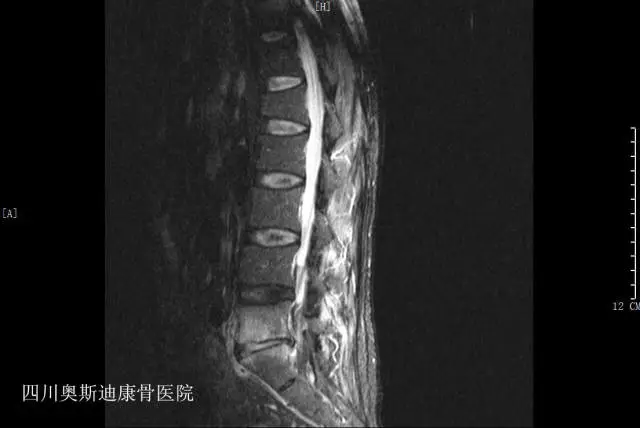

影像学所见:L4-5、L5-S1椎间盘膨出、突出(中央型),椎管狭窄;腰椎退变,L3-S1椎间盘变性,L5-S1椎间盘及终板改变考虑退变可能,不除外椎间盘终板炎;腰骶部软组织水肿;L1椎体陈旧压缩骨折。

诊断:L5-S1椎间盘炎、L4-S1椎间盘突出症